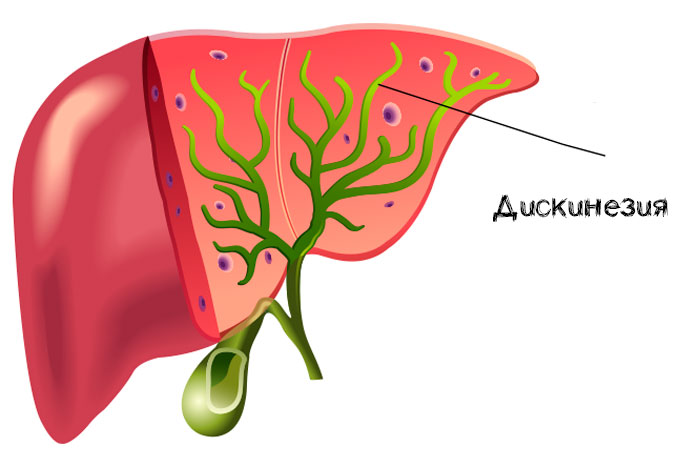

Фотографии и изображения, связанные с симптомами первичного склерозирующего холангита